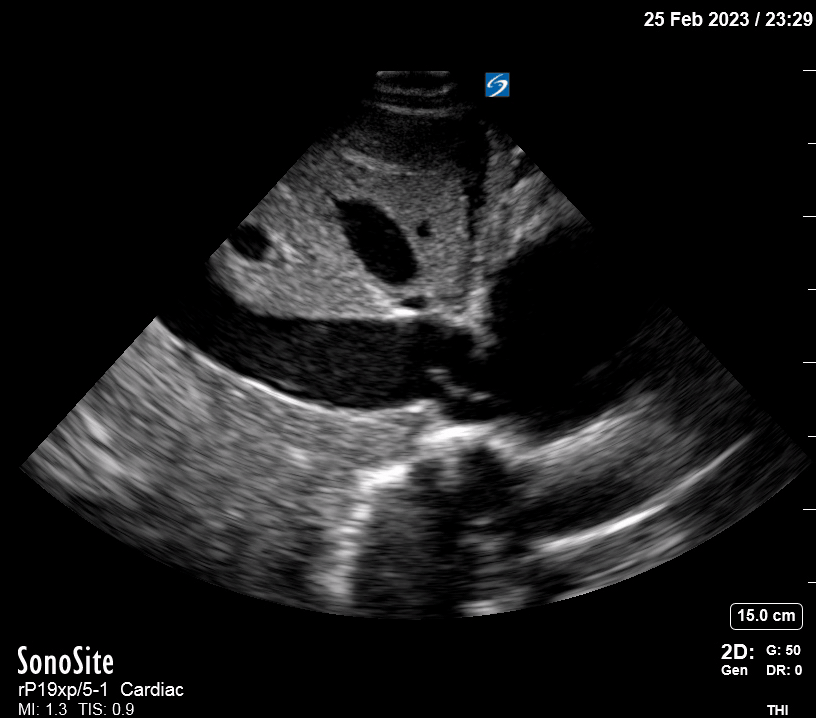

Exit: is there acute aortic root pathology?

Thoracic Aortic dissection is a time-dependent and deadly pathology that can occur silently or be masked by a variety of clinical presentations. While angio-CT remains the gold standard for diagnosis, US may be performed quicker and at the bedside. In the visible portion of the aortic root, the US findings can include intimal flap, aortic valve insufficiency, retrograde aortic flow, or rupture into the pericardium with pericardial effusion and tamponade. Alternatively, dilation of the aortic root is characteristic of a thoracic aortic aneurysm.

Importantly, remember that thoracic aortic dilation or intimal flap may occur distal to the aortic root, where an US scan is usually blind. Hence, the absence of dilation or flap does not rule out aortic disease.

THE VIEWS

The PLAX view is best for exploring the aortic root. If performed by an experienced operator, aortic root measurements in this window correlate well with angio-CT measurements.

The Aortic root size varies with age and gender and should be measured at its widest point, perpendicular to its long axis. In general, a root > 4 cm should be considered borderline and enough to warrant a formal study.

Alternatively, the aortic root size can be estimated by the rule of thirds, where in the PLAx view the size of the RV, AoR, and LA should be roughly 1:1:1.

AORTIC DISSECTION

In both of these views, US may detect an intimal flap seen as a hyperechoic linear structure within the aortic lumen that moves with each heartbeat. The visualization of a flap carries a high specificity and should prompt immediate consultation with cardiothoracic surgery; however, ultrasound sensitivity for intimal flap is significantly low, and its absence does not rule out aortic dissection.